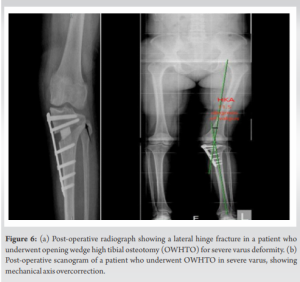

There are several limitations to our study. This study’s retrospective design and sample size, limit generalizability. In addition, while statistical projections provided insights into DLO’s 10-year outcomes, direct long-term data would yield more definitive conclusions. Future research with larger, prospective cohorts and extended follow-up periods for DLO patients is recommended to validate these projections and confirm the observed outcome stability (Figs. 6a and b).